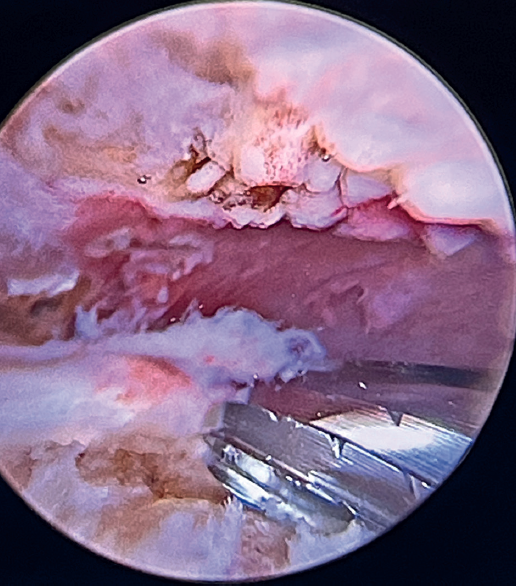

Tension-free repair of the supraspinatus tendon is then made, using the free thread left at the anchoring and taking advantage of the two sutures passed through and knotted to the proximal LPB fragment (Figures 8, 9 and 10).

The free suture remaining at the anchoring is passed through the anterolateral supraspinatus using a Scorpion® direct suture passer (Arthrex, Naples, FL, USA), as a sliding mattress suture over the implant.

One end of each of the sutures exiting the LPB is passed through the supraspinatus likewise using a Scorpion® direct suture passer (Arthrex, Naples, FL, USA). All the threads are left unknotted and are recovered through the anterior working portal so that they do not get in the way when working later on. Note that the two threads exiting the LPB and passing through the supraspinatus will not slide; it is therefore advisable to knot them and lower them later on with a knot pusher. This point allows repair of the anterior supraspinatus to be combined with fixation of the LPB in the anterolateral zone of the greater tuberosity.

A second anchorage loaded with two tapes is implanted at the same height as the first, but in a more posterior position. Again using direct suturing with mattress stitches, we repair the posterolateral part of the supraspinatus and even the anterior part of the infraspinatus, if necessary.

Having passed both the anterior and the posterior sutures, we proceed to knot, through the lateral portal with a working cannula, each of the sutures, starting posterior and ending anterior.